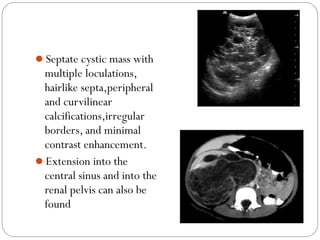

Septate cystic mass with

multiple loculations,

hairlike septa,peripheral

and curvilinear

calcifications,irregular

borders, and minimal

contrast enhancement.

Extension into the

central sinus and into the

renal pelvis can also be

found